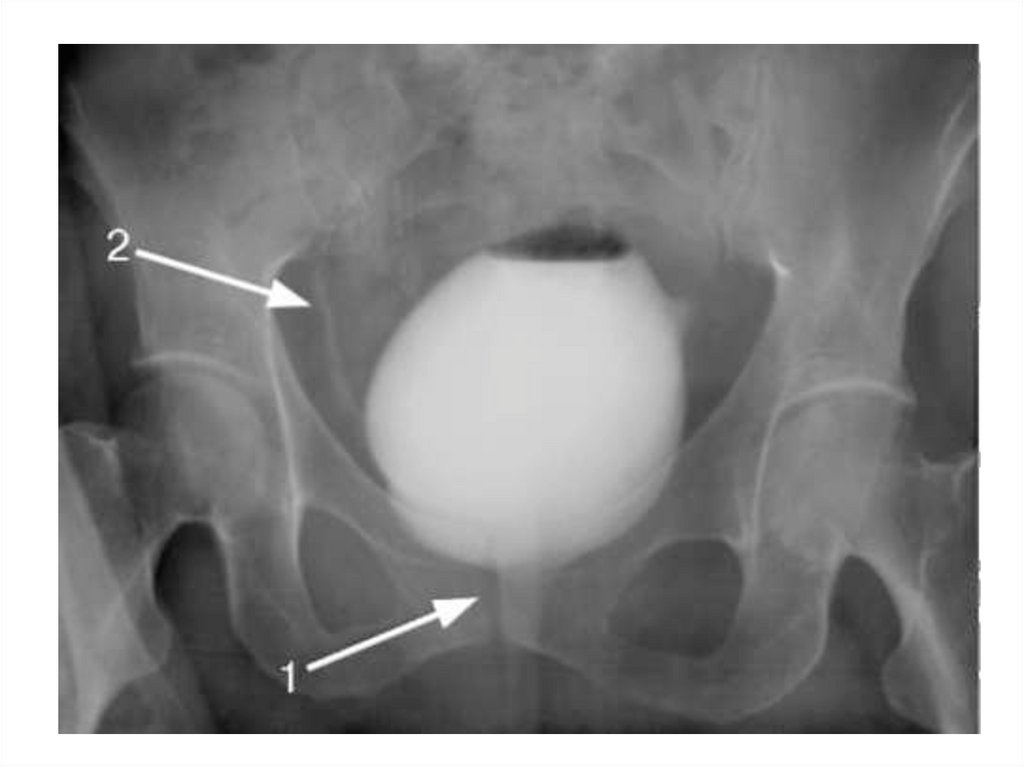

Цистография

Контрастное исследование

мочевого пузыря.

• Пузырно-мочеточниковый

рефлюкс?

• Форма

• Контуры

• Дефекты контрастирования

• Грыжа, дивертикул

21.